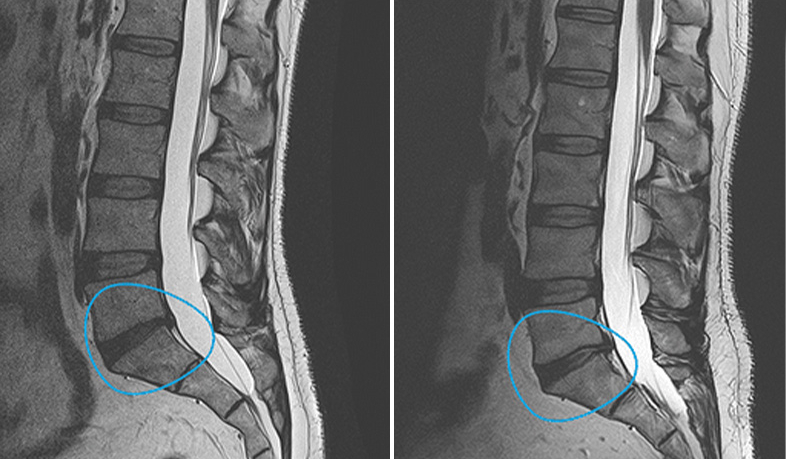

Lesiones de disco intervertebralEn degeneración discal lumbar, la administración intradiscal de CMC ha mostrado recuperación estructural en resonancia magnética y una reducción mantenida del dolor, con seguimiento clínico prolongado.